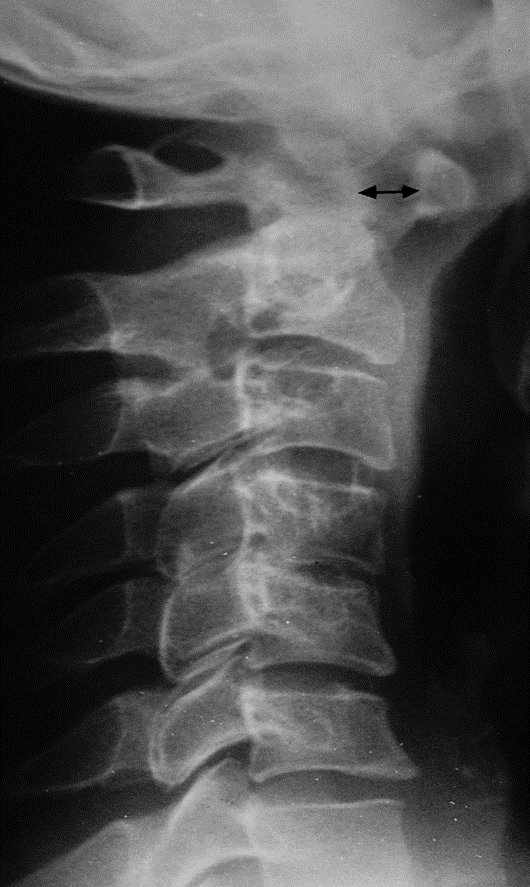

Atlantoaxial subluxation.

C1 is displaced anteriorly upon C2. The distance between the arch of the atlas and the odontoid peg (arrow) is increased from the normal value (2 mm) to 8 mm.